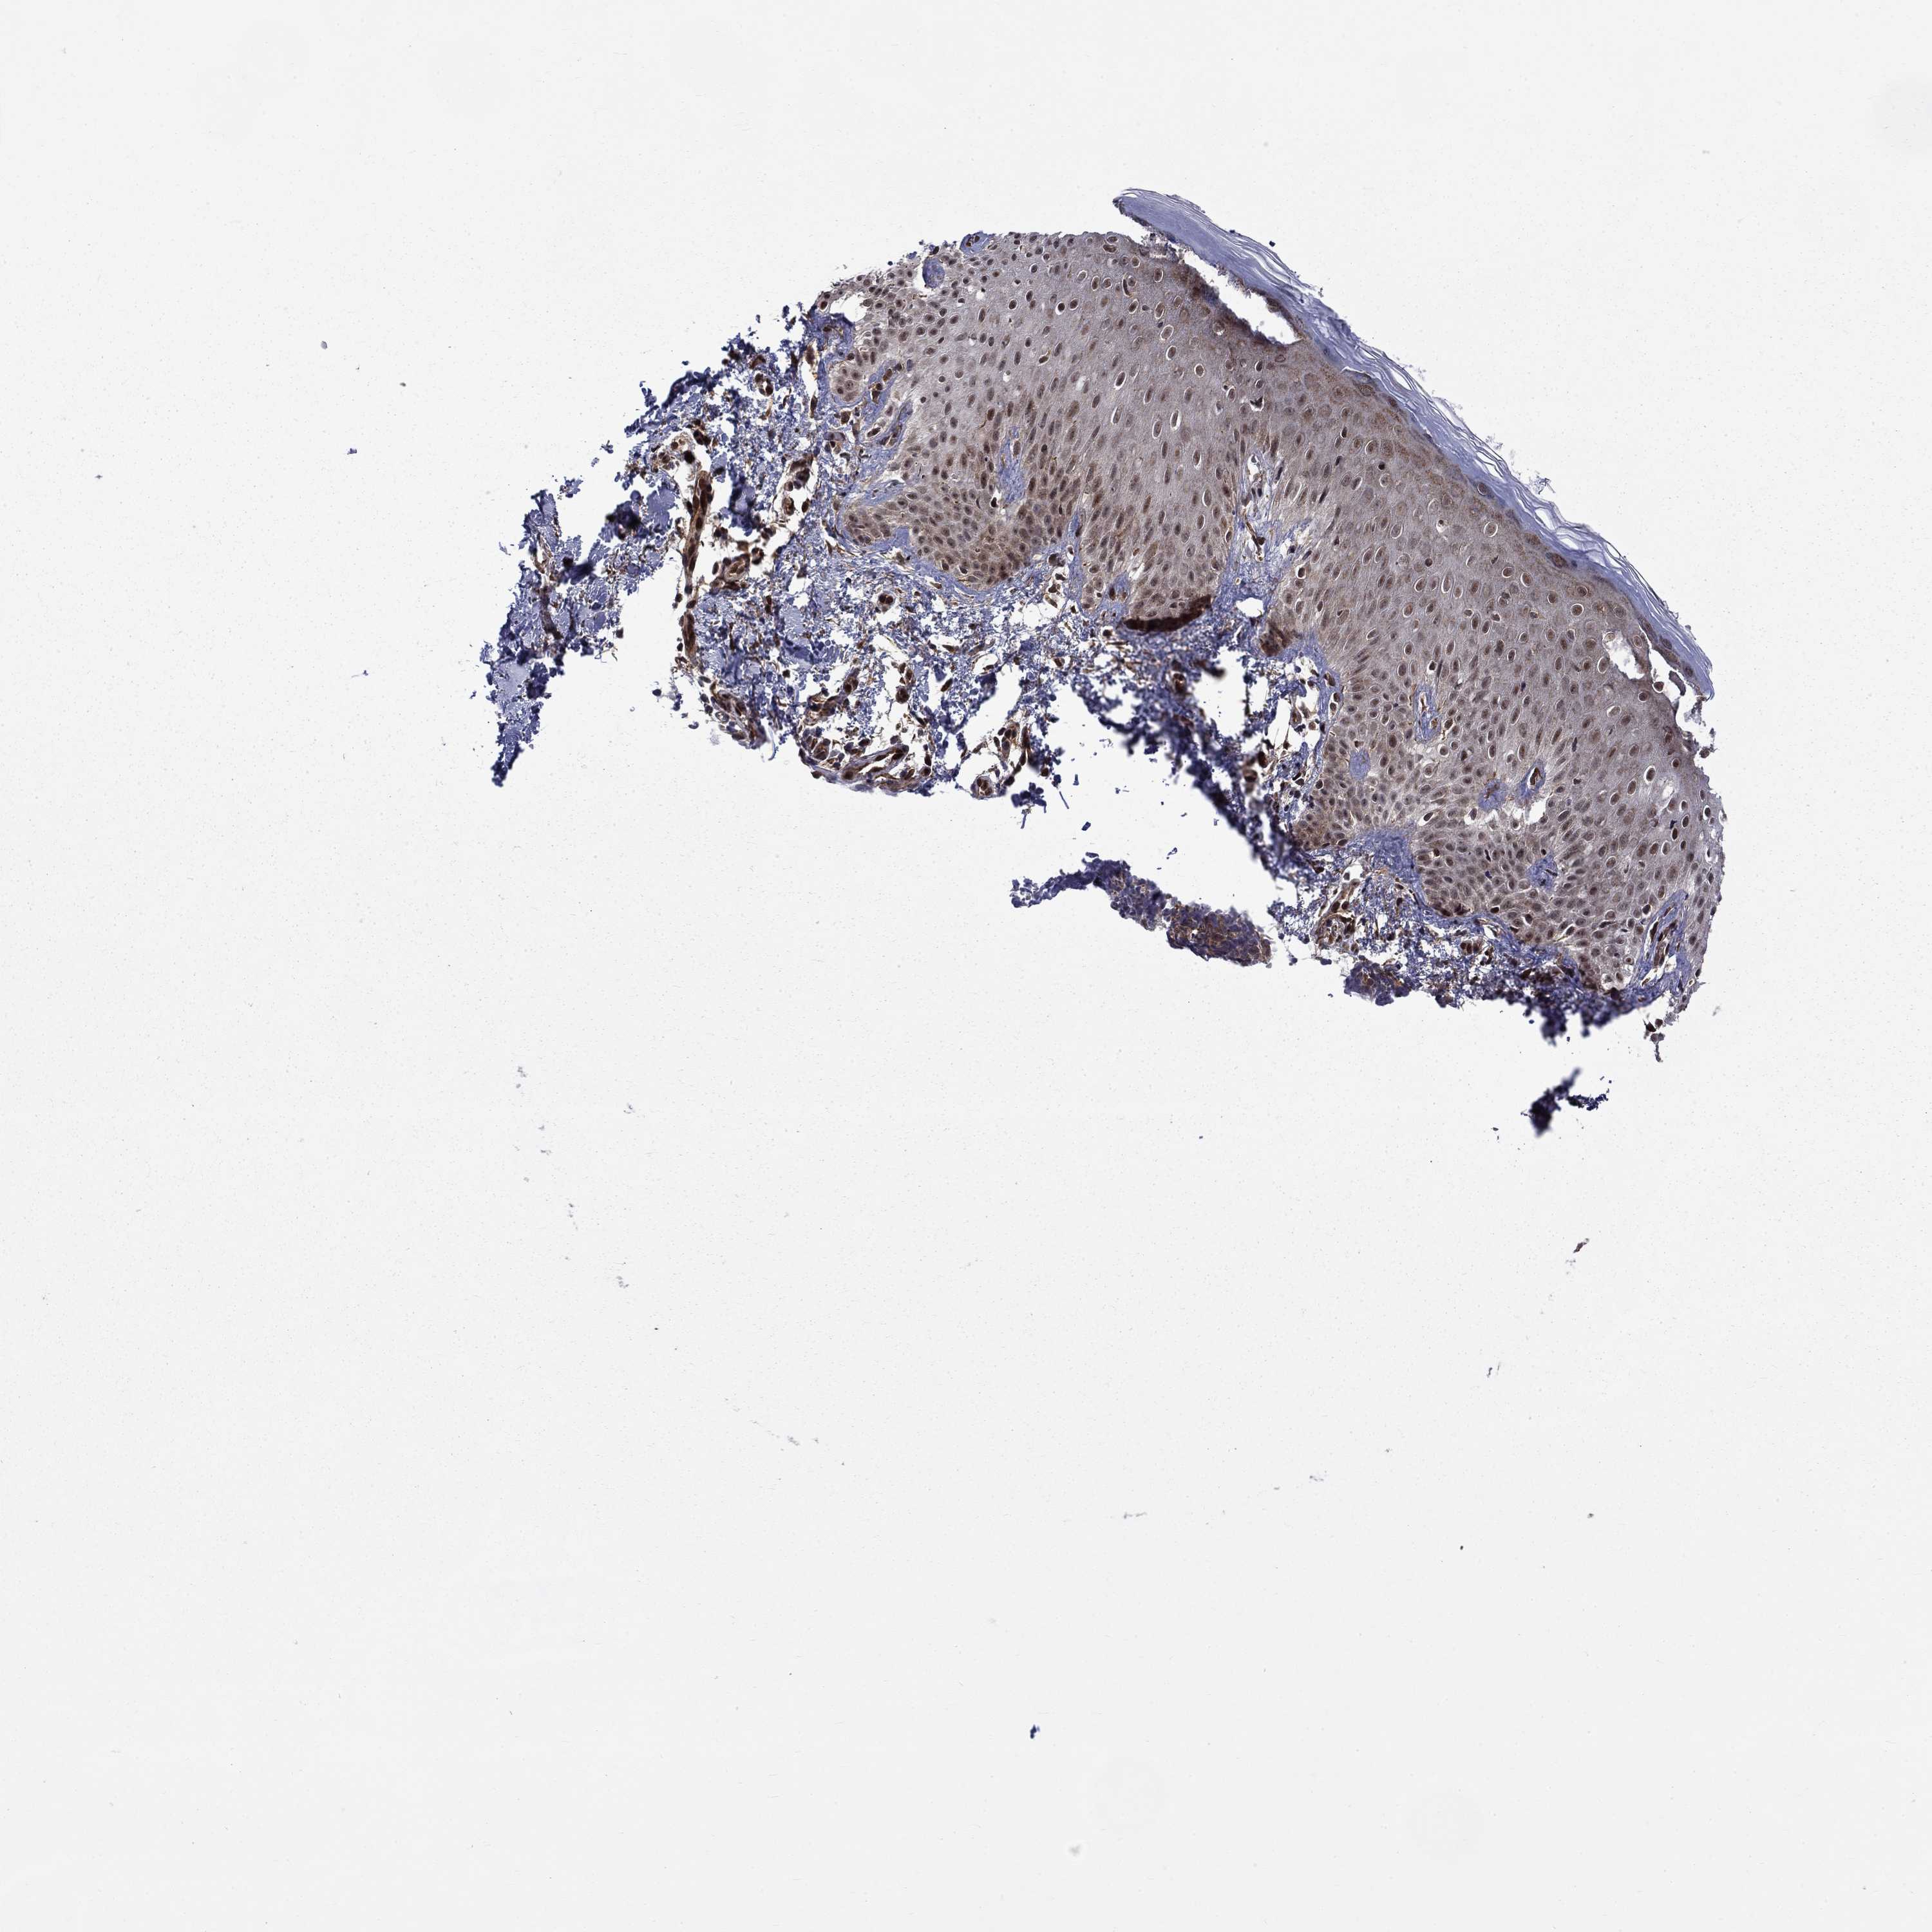

MELANOMA - Protein expressioni

A mouse-over function shows sample information and annotation data. Click on an image to view it in a full screen mode. Samples can be filtered based on level of antibody staining by selecting one or several of the following categories: high, medium, low and not detected. The assay and annotation is described here.

Note that samples used for immunohistochemistry by the Human Protein Atlas do not correspond to samples in the TCGA dataset.

Antibody stainingi

Antibody staining in the annotated cell types in the current human tissue is reported as not detected, low, medium, or high, based on conventional immunohistochemistry profiling in selected tissues. This score is based on the combination of the staining intensity and fraction of stained cells.

Each image is clickable and will lead to virtual microscopy that enables deeper exploration of all samples and also displays staining intensity scores, fraction scores and subcellular localization as well as patient and tissue information for each sample.

Antibody HPA046852

Antibody HPA077643

Staining

High

Medium

Low

Not detected

Intensity

Strong

Moderate

Weak

Negative

Quantity

>75%

75%-25%

<25%

None

Location

Nuclear

Cytoplasmic/membranous

Cytoplasmic/membranous,nuclear

Malignant melanoma, NOS

Malignant melanoma, Metastatic site